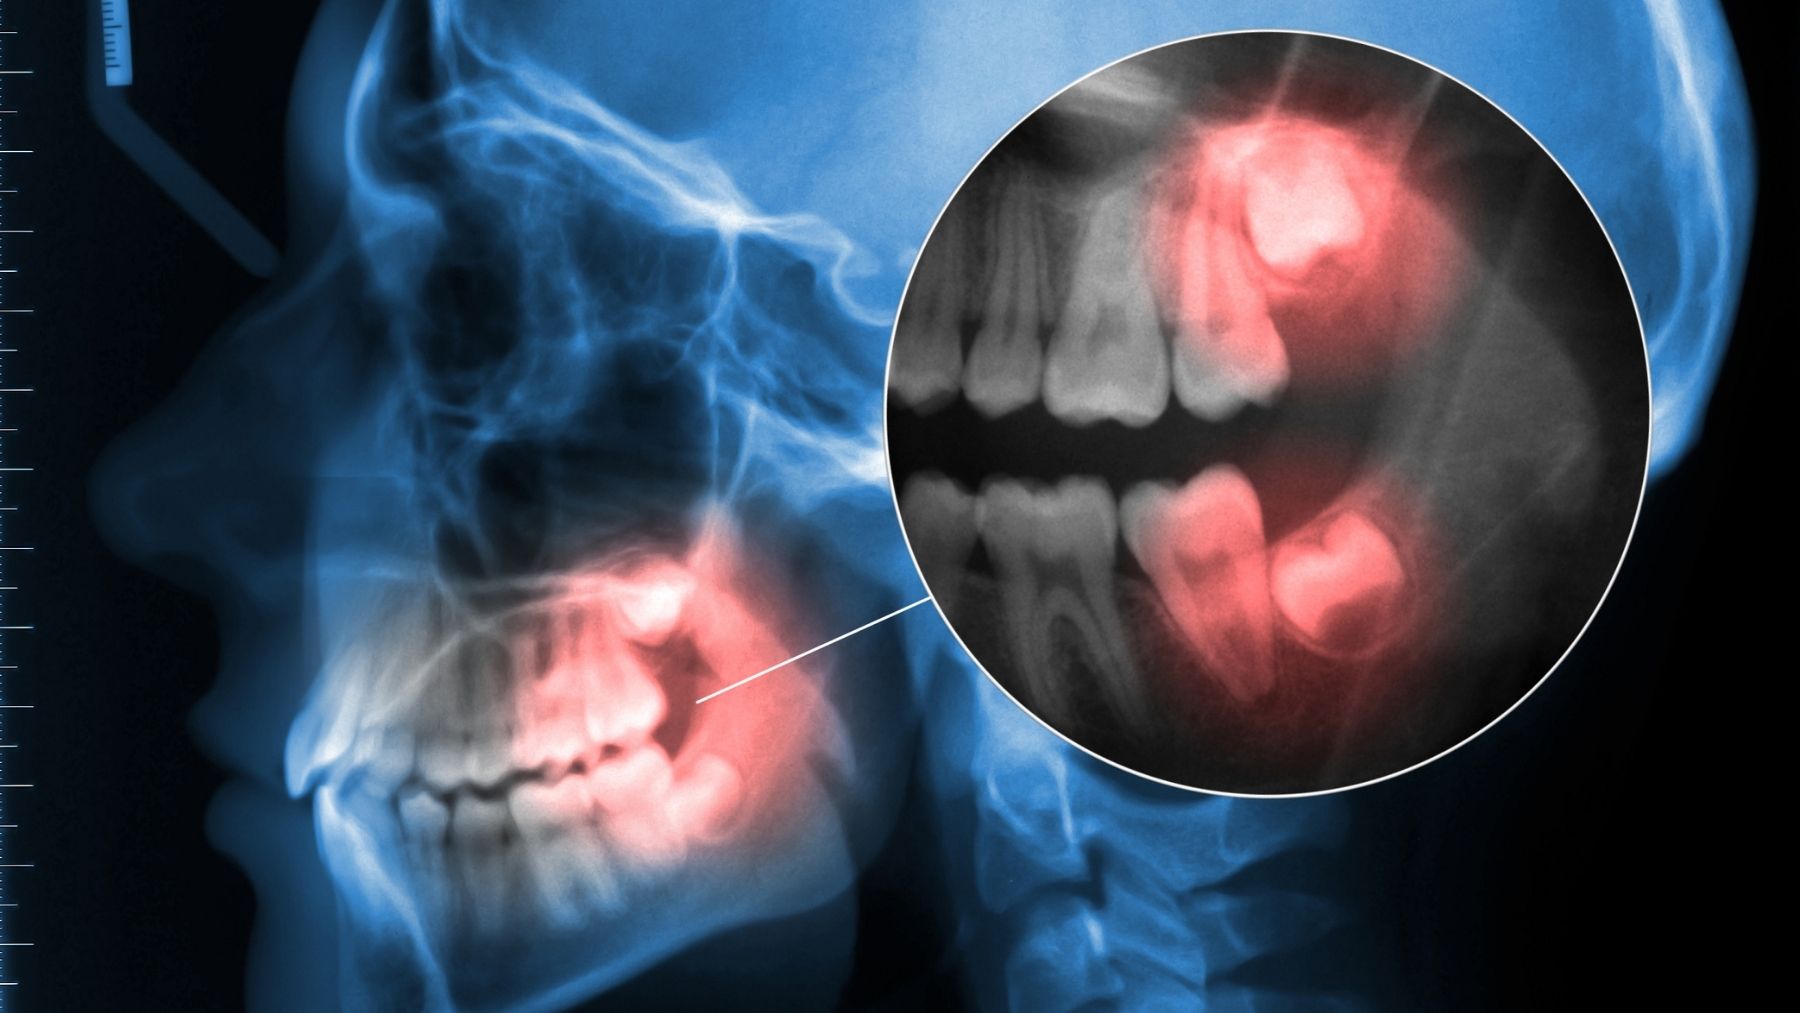

Las muelas del juicio, que suelen aparecer en la boca entre los 17 y 25 años, han sido tradicionalmente un dolor de cabeza tanto para dentistas como para pacientes. Son los últimos en erupcionar, y con frecuencia, su aparición viene acompañada de dolor e infecciones. Durante años, se ha considerado que las muelas del juicio son una parte del cuerpo humano que no tiene mucho propósito más allá de generar problemas. Se creía que, en su origen, estos dientes ayudaban a nuestros antepasados a triturar alimentos más duros, como raíces o carne cruda.

Sin embargo, la evolución de nuestra dieta y el cambio en la estructura de nuestras mandíbulas han hecho que estas piezas dentales se vuelvan prácticamente obsoletas. Sin embargo, investigaciones recientes están cambiando la percepción de estas piezas dentales, que podrían tener un gran valor en el ámbito de la medicina regenerativa. Este hallazgo promete abrir nuevas posibilidades en el tratamiento de enfermedades como el párkinson, el alzhéimer y la insuficiencia cardíaca, gracias a las células madre que contienen en su tejido pulpar.

La pulpa dental de las muelas del juicio contiene un tipo específico de células madre conocidas como células madre mesenquimatosas. Estas células tienen la capacidad de diferenciarse en varios tipos celulares, lo que les otorga un potencial terapéutico asombroso. Entre las transformaciones posibles se incluyen la regeneración de hueso, cartílago y tejido adiposo, que son fundamentales en diversas enfermedades.

Las muelas del juicio, por tanto, no sólo contienen células madre con aplicaciones en la regeneración ósea, sino que también tienen la capacidad de contribuir a la regeneración de tejidos cartilaginosos y grasos, lo que podría ser crucial para tratar afecciones como la osteoartritis o incluso enfermedades cardiovasculares.

Procedimiento de extracción

Una de las grandes ventajas de utilizar las muelas del juicio para obtener células madre es la facilidad con la que se pueden extraer. En la mayoría de los casos, la extracción de las muelas del juicio se lleva a cabo durante la juventud, un momento en que el tejido pulpar es más viable y menos deteriorado.

Esto significa que las células madre extraídas de estos dientes tienen una mayor capacidad de regeneración, lo que mejora sus posibilidades de éxito en aplicaciones médicas. Además, la extracción de las muelas del juicio es un procedimiento relativamente sencillo, que se realiza en un entorno controlado y estéril, lo que garantiza la calidad y seguridad del proceso.

La extracción no sólo es menos invasiva que otros procedimientos médicos que requieren la toma de células madre de otras partes del cuerpo, sino que también se puede realizar en pacientes jóvenes, lo que asegura que las células no se hayan deteriorado con el paso de los años. Esta accesibilidad convierte a las muelas del juicio en una fuente ideal para obtener material biológico sin las complicaciones asociadas con otras opciones más invasivas.